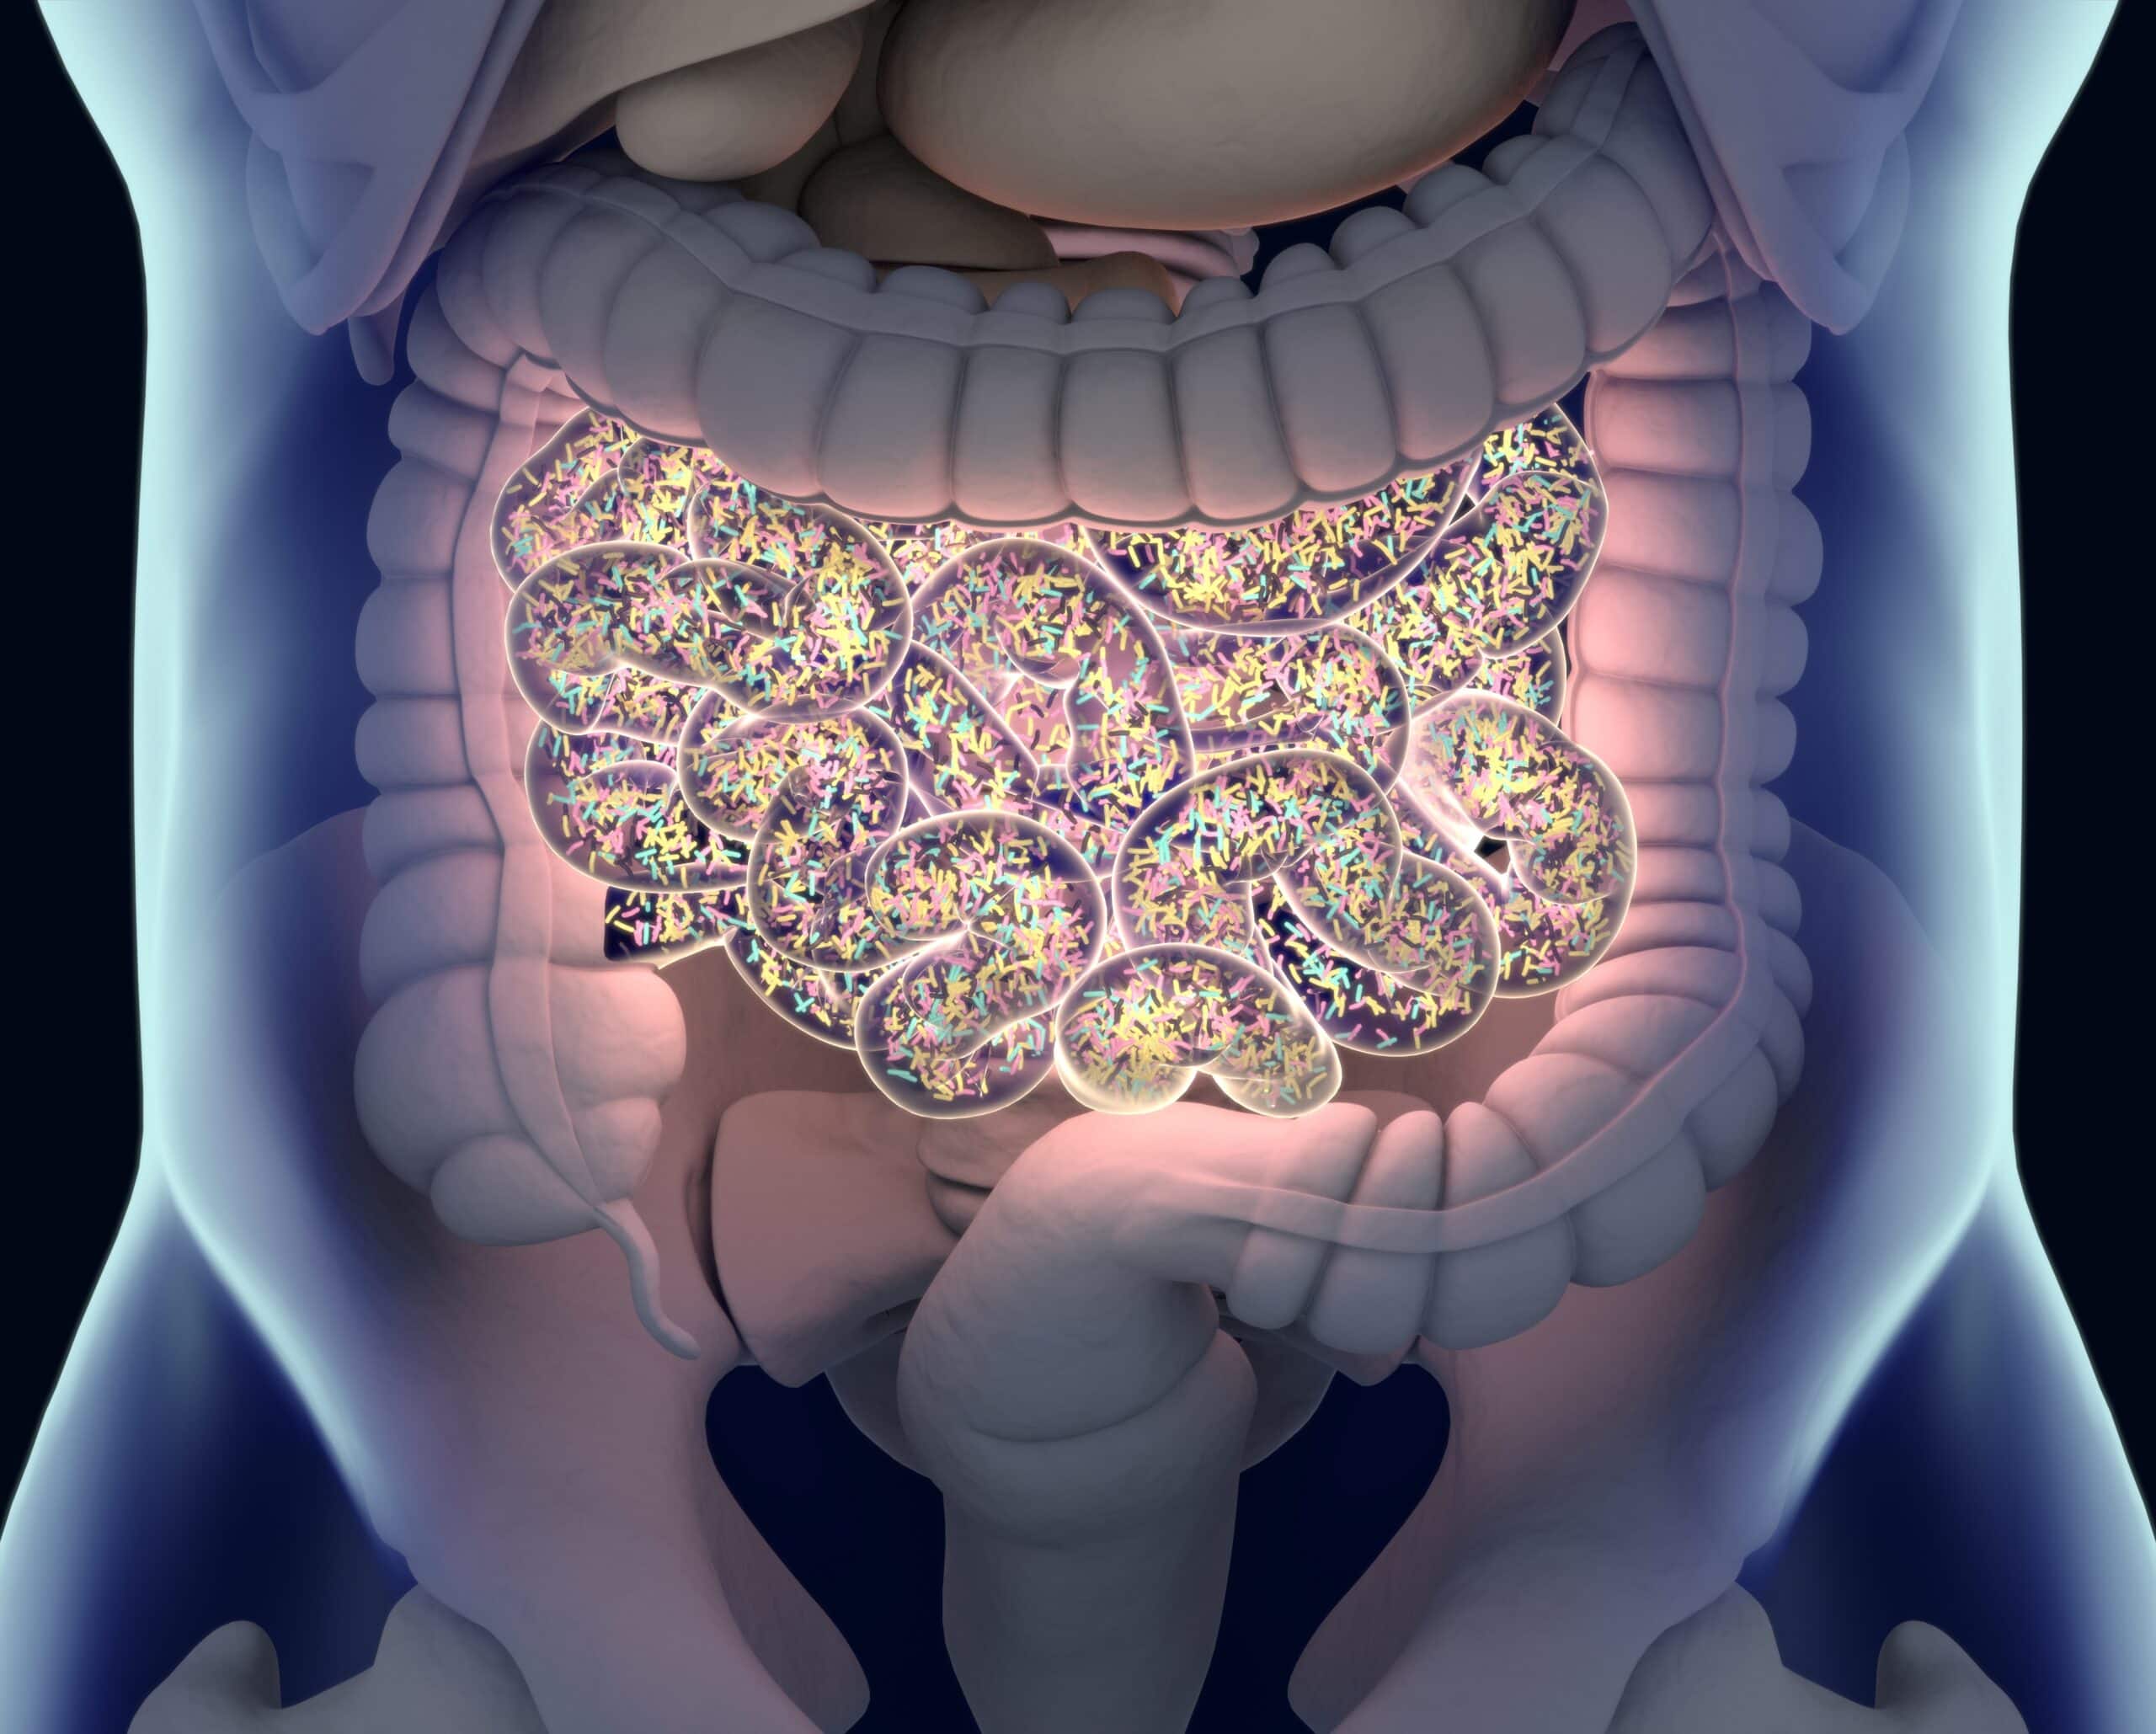

- Naukowcy na całym świecie zgadzają się obecnie, że jelita i żyjące w nich bakterie mają duży wpływ na cały organizm.

Mikrobiom jelitowy odnosi się do ogółu wszystkich żywych organizmów znajdujących się w naszych jelitach. Są to głównie bakterie; zdrowy mikrobiom jelitowy zawiera do 100 różnych szczepów! Należy zauważyć, że aby jelita spełniały swoje funkcje, wymagany jest precyzyjnie zrównoważony poszczególnych szczepów bakterii.

Jeśli jeden szczep jest nadreprezentowany lub jest go zbyt mało, lub jeśli ogólnie nie ma wystarczającej liczby bakterii, mikrobiom staje się niezrównoważony. Taka nierównowaga, znana również jako dysbioza, może mieć różne skutki - nie tylko w oczywistych obszarach, takich jak trawienie, ale także w naszym nastroju, układzie odpornościowym i wielu innych obszarach. Ale co to wszystko ma wspólnego z naszą wagą?